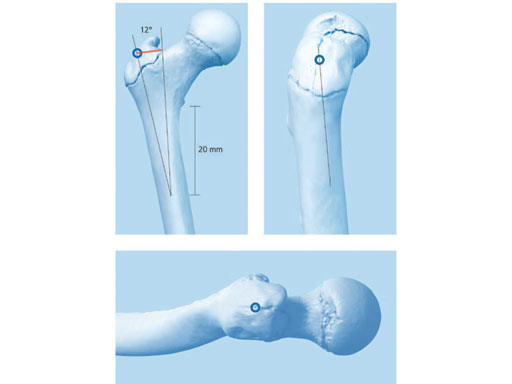

Conventional antegrade nailing of the femur in this age group is a concern because of the possibility of avascular necrosis of the femoral head. This is rare but devastating. The ALFN has a lateral trochanteric entry point and a double curved configuration (double bend in two planes and additional tip bend) to avoid compromising the ascending branch of the medial femoral circumflex artery near the piriformis fossa. The recommended entry site is on the bare aspect of the greater trochanter 1520 mm distal to the tip of the greater trochanter and forms an angle of 1214 lateral to the greater trochanter, as measured from the lateral entry point to a point 20 mm distal to the lesser trochanter (Fig 2).